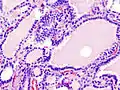

Hyperthyroidism is one of the most common endocrine conditions affecting older domesticated housecats. In the United States, up to 10% of cats over ten years old have hyperthyroidism.[60] The disease has become significantly more common since the first reports of feline hyperthyroidism in the 1970s. The most common cause of hyperthyroidism in cats is the presence of benign tumors called adenomas. 98% of cases are caused by the presence of an adenoma,[61] but the reason these cats develop such tumors continues to be studied.